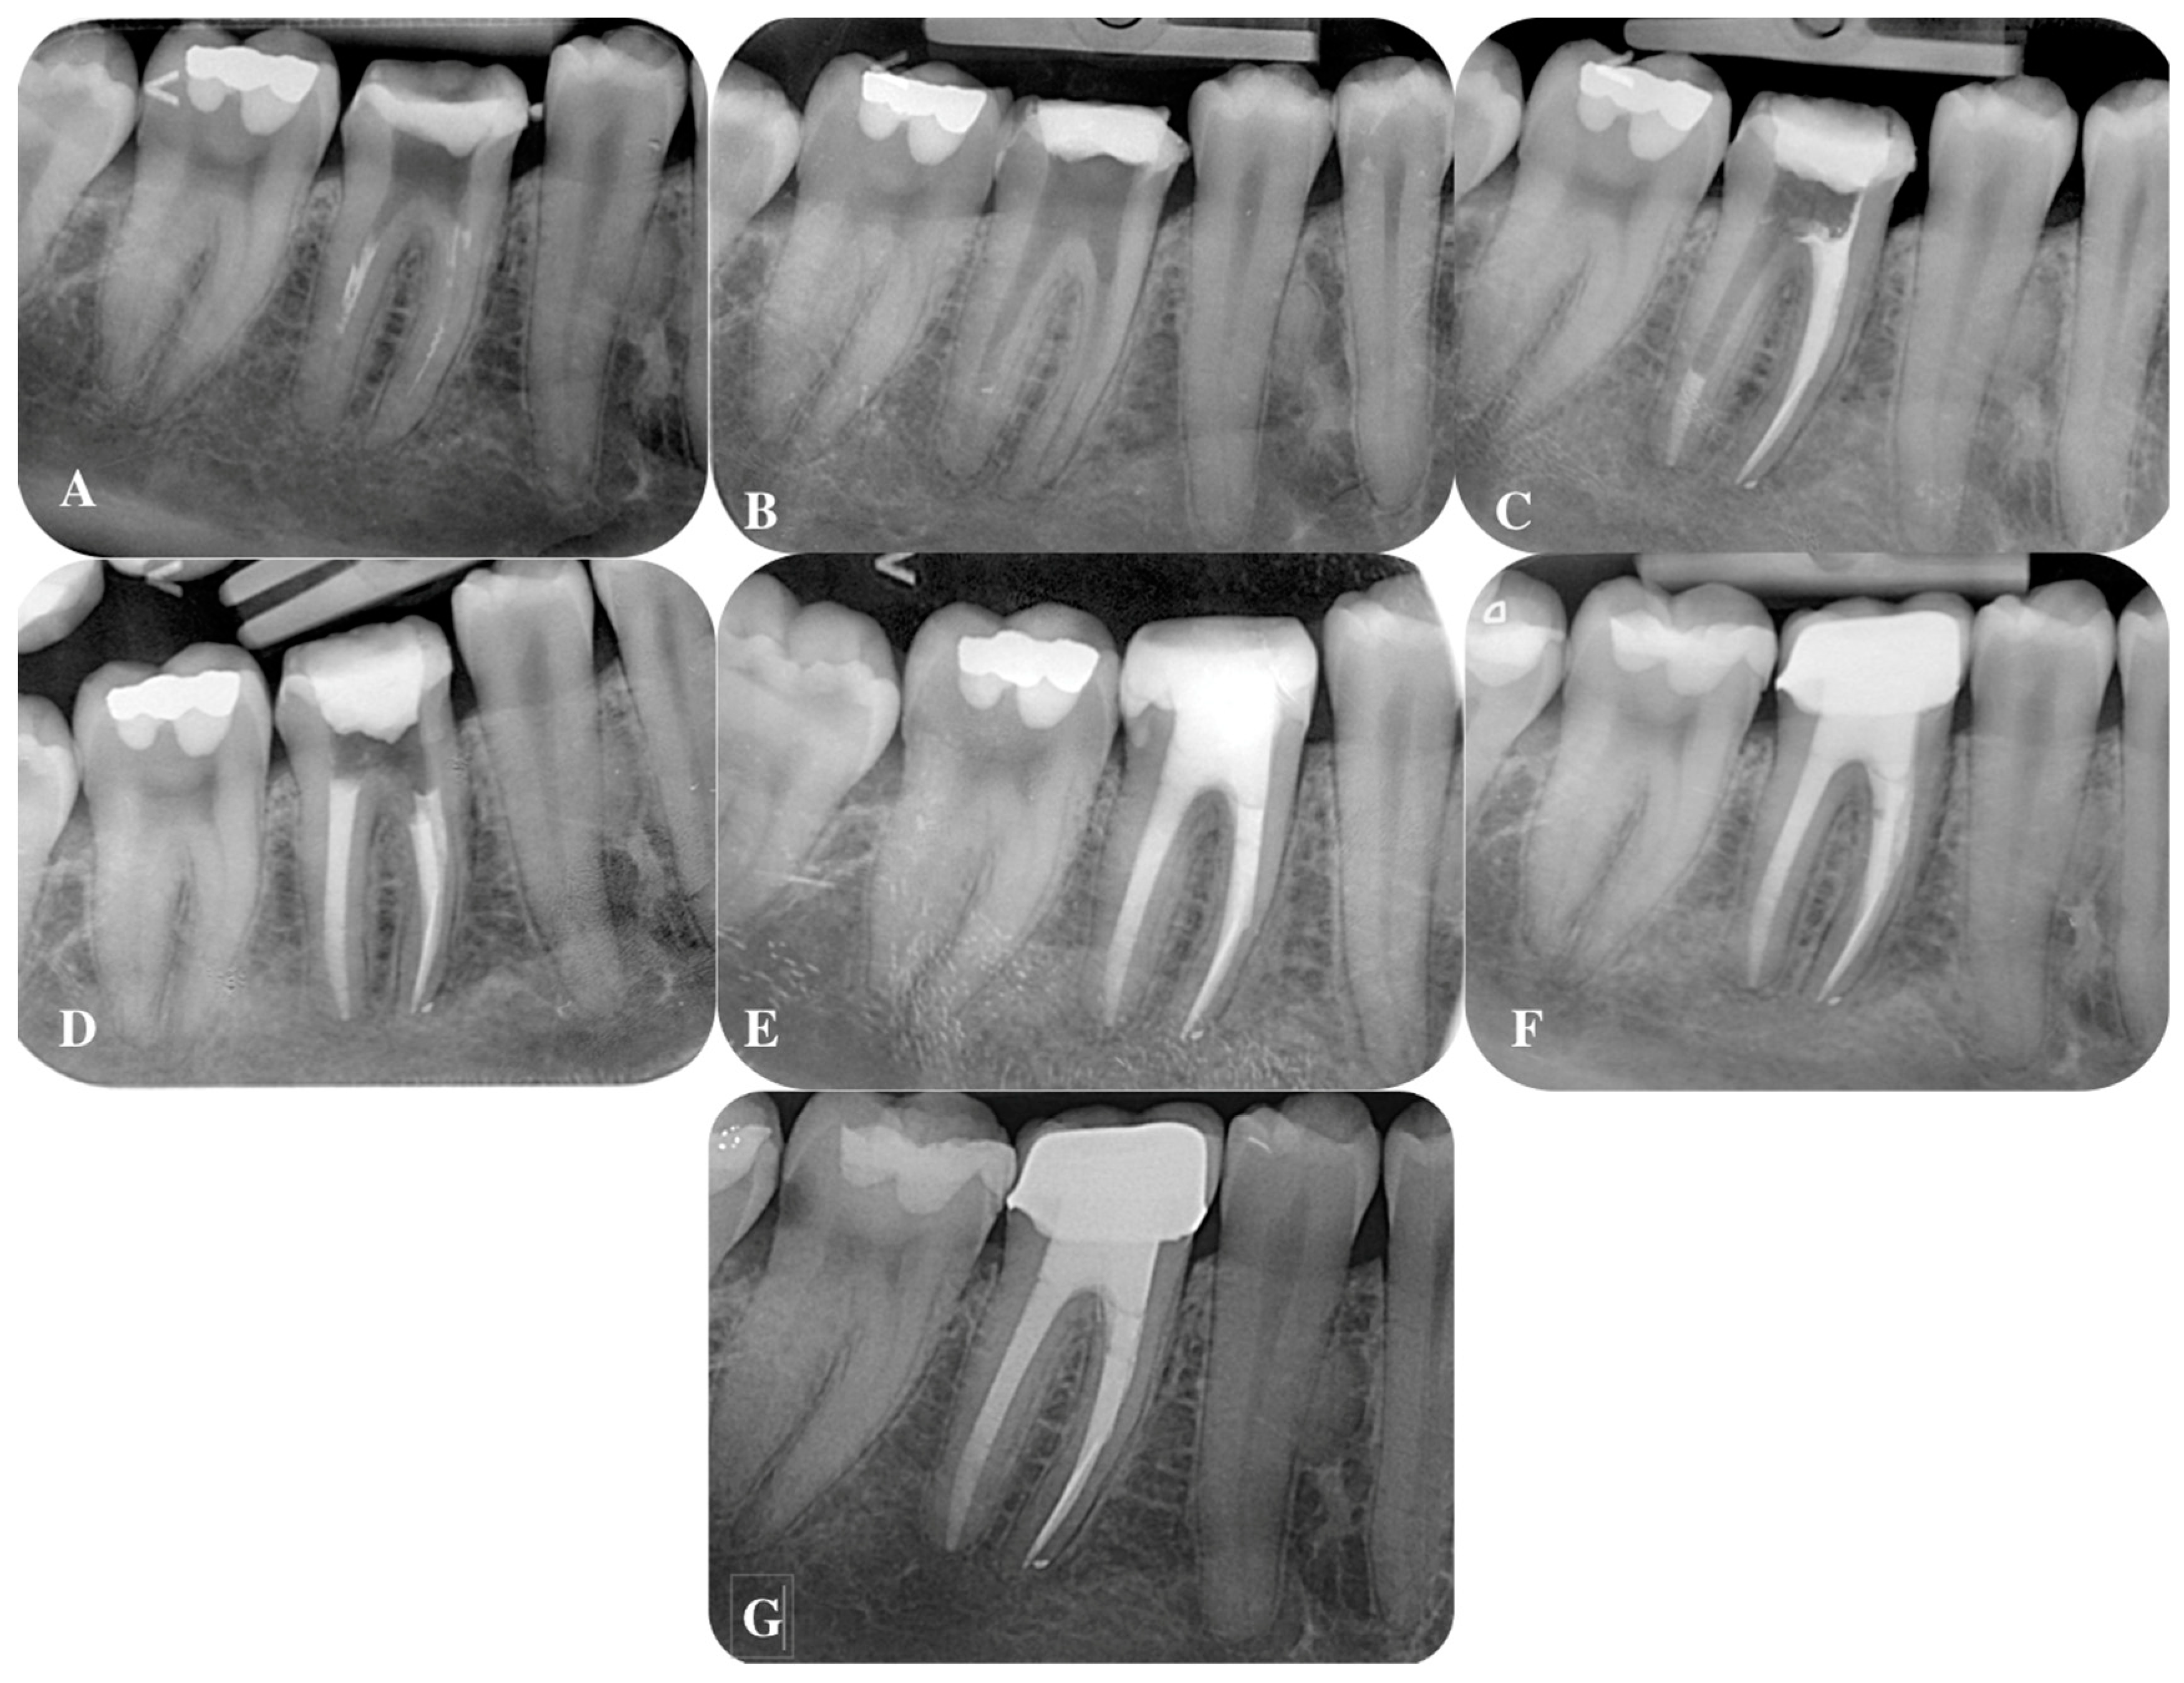

5. Apical Plug in Teeth with Periapical Lesions

5.1. Apical Plug in Teeth with Apical Resorption and “Open Apex”

5.2. Apical Barrier